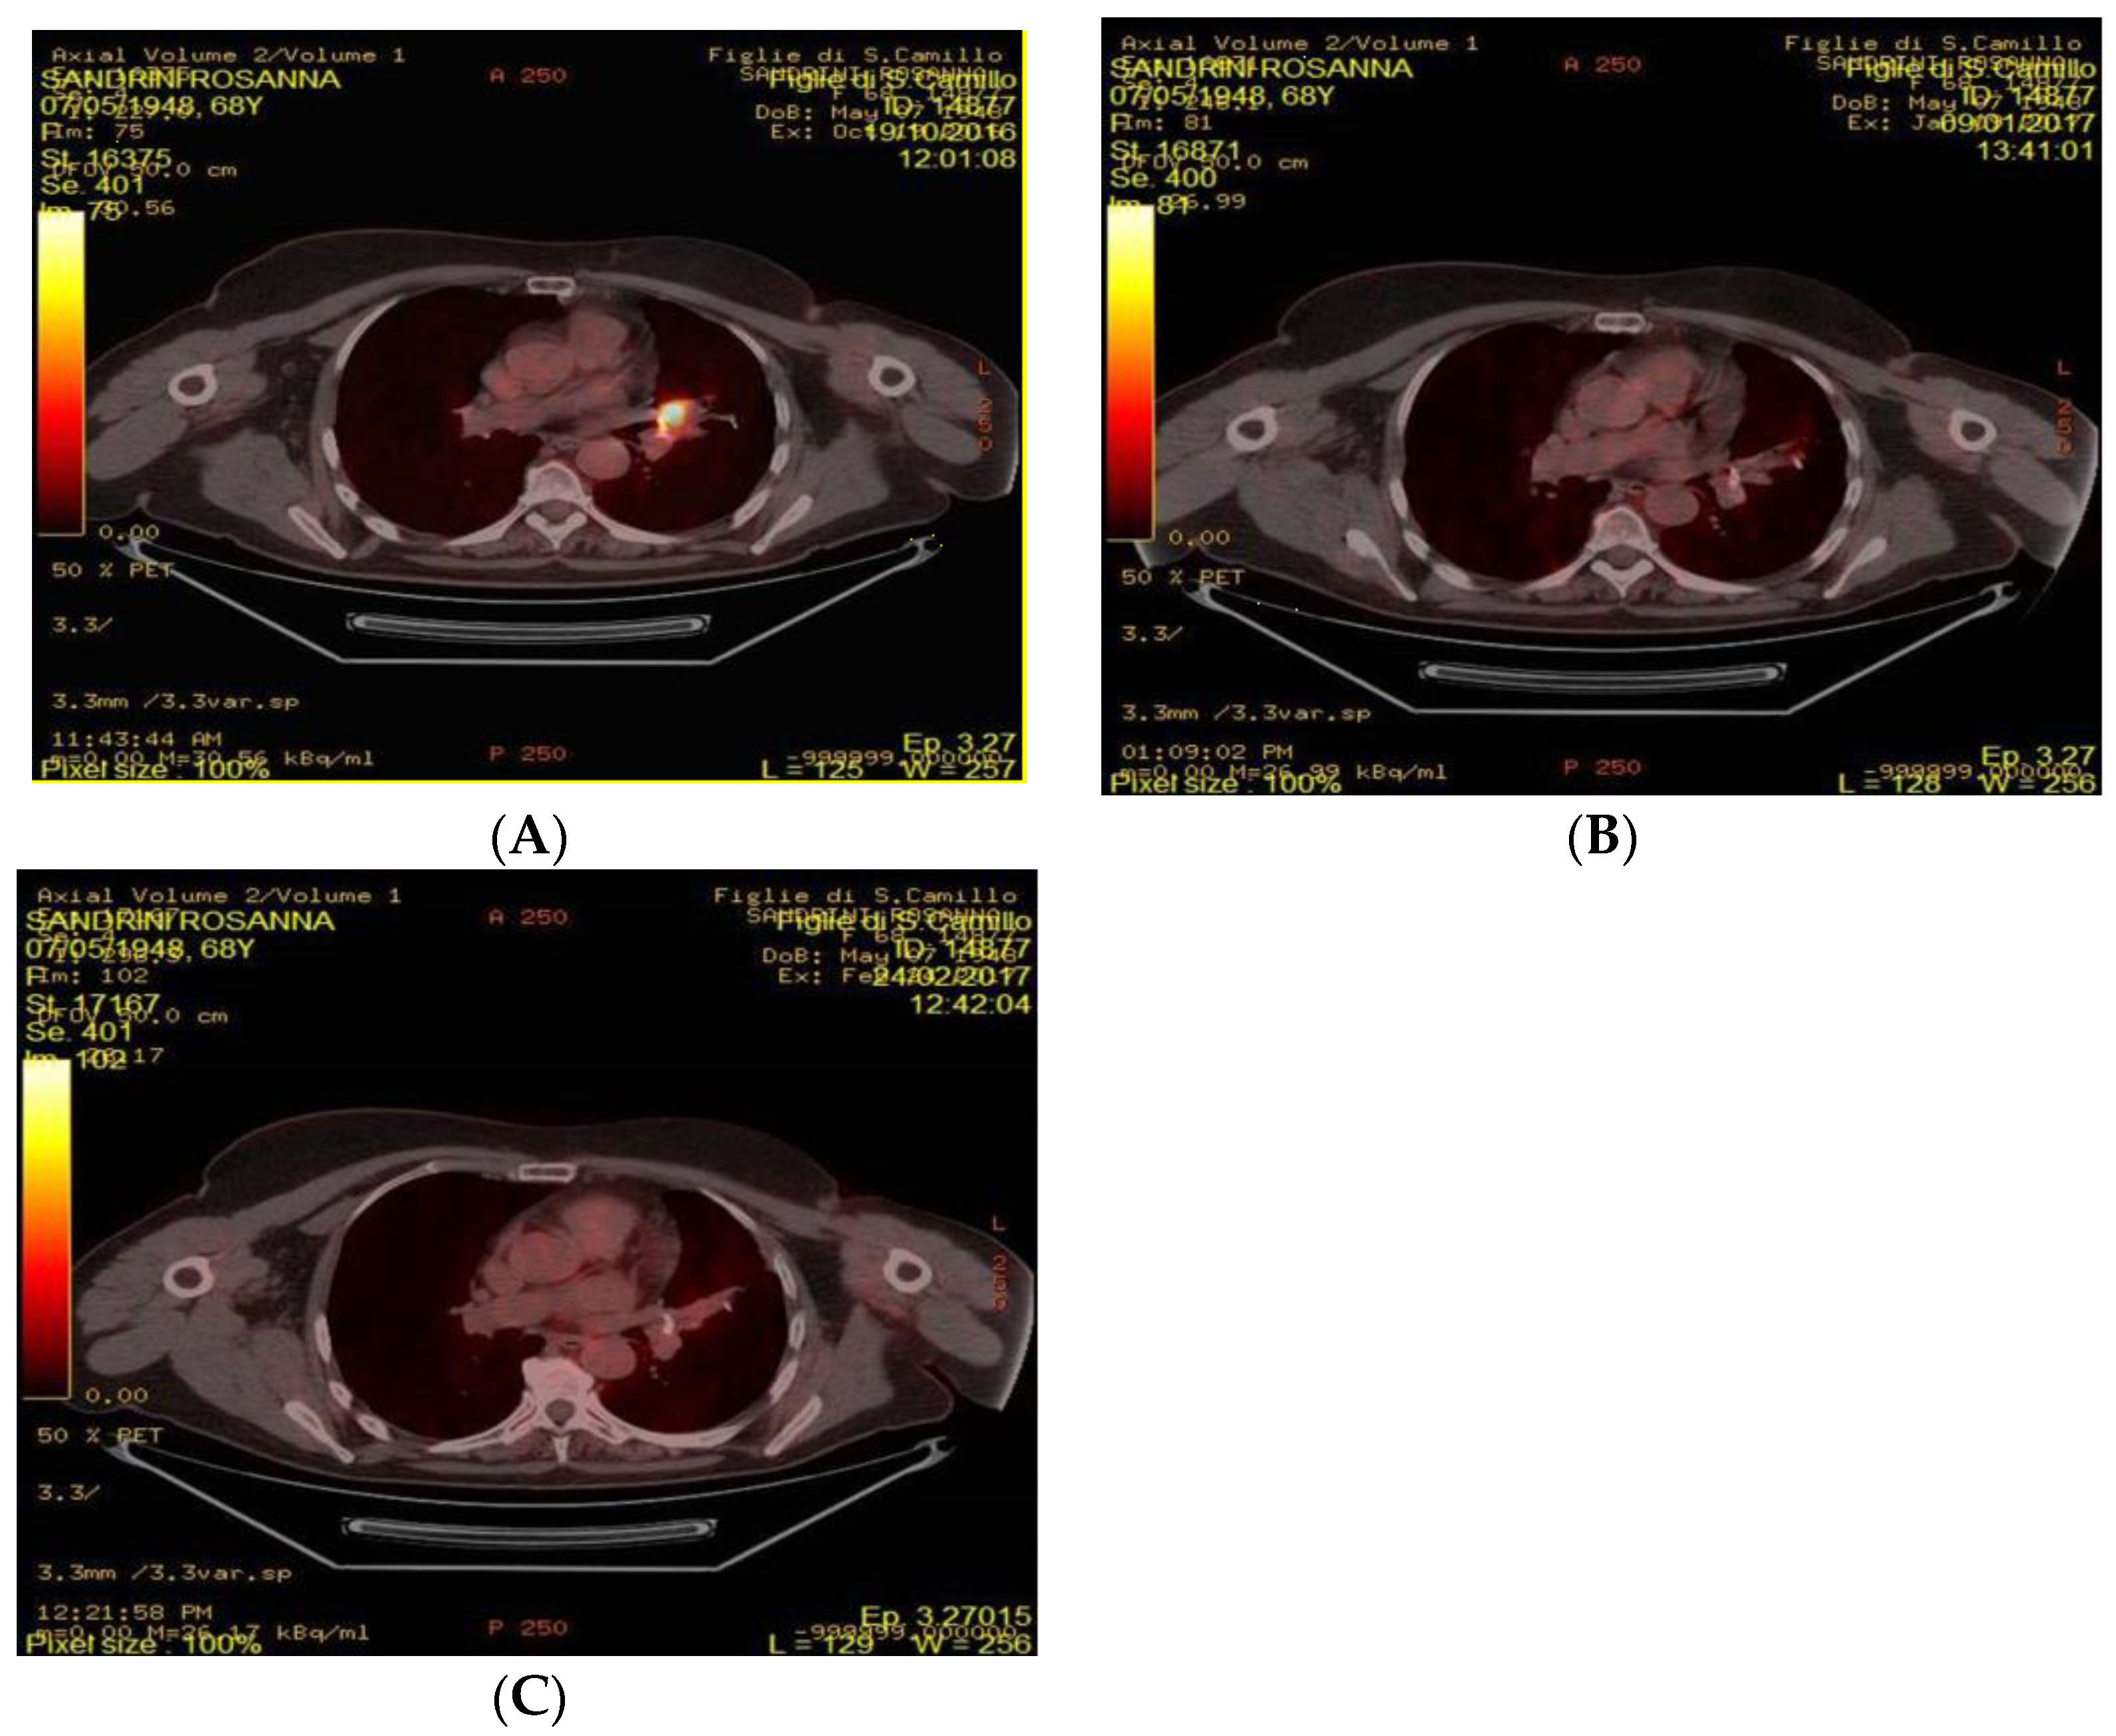

4.2. FDG-PET/CT Acquisition and Analysis